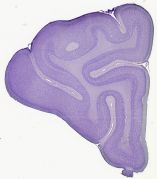

Datasets -> Felis Catus -> CV, (Cresyl Violet), coronal, histo, Single-hemisphere, adult

[ Metadata ]   ·   Source: R. Glenn Northcutt Collection, MCZ-Harvard   ·   [ R. Glenn Northcutt Collection info ]

Displaying Sections 1 thru 40 of 86 Sections for this Dataset